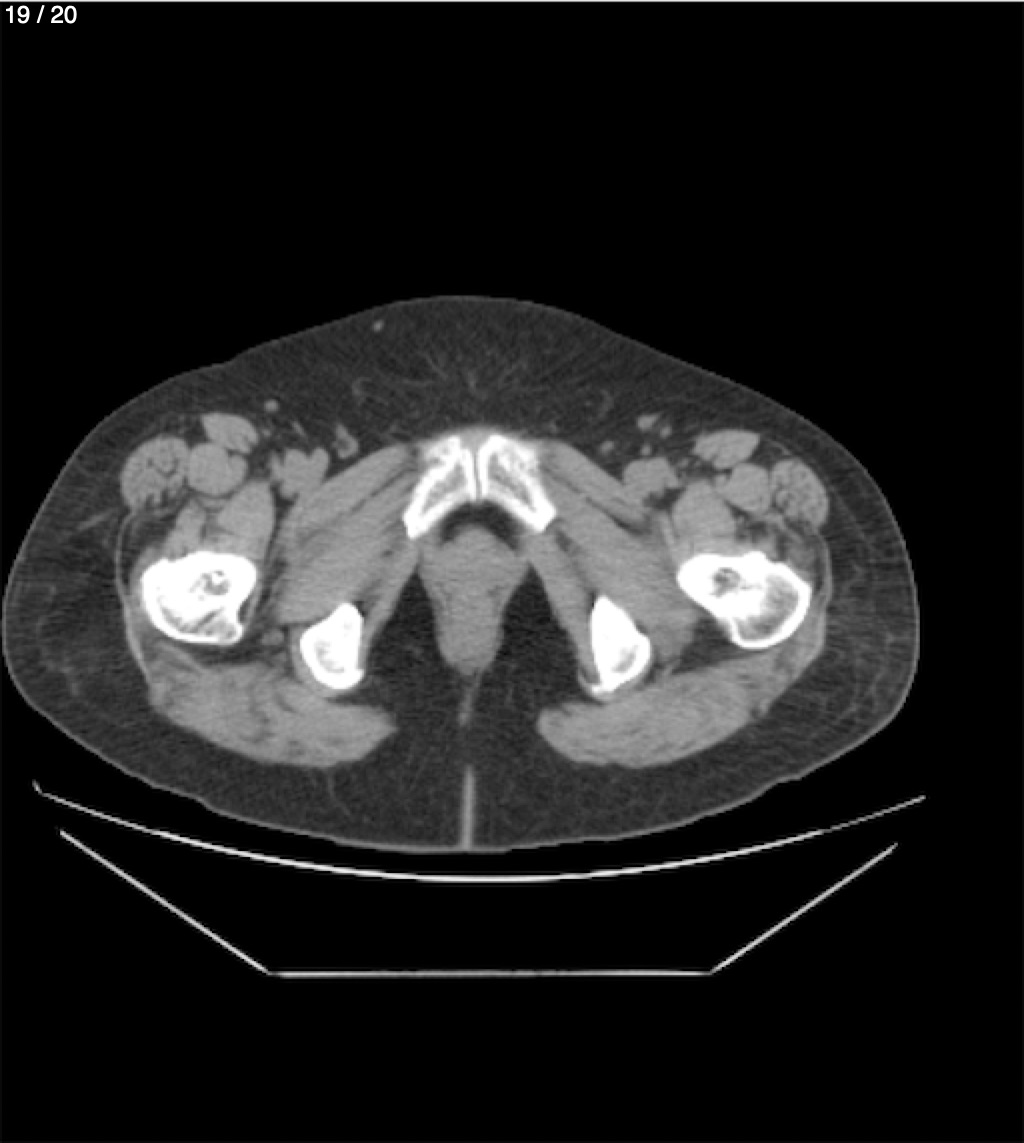

Maria Enrique Giron Dominguez63A - T.C Abdomen Simple